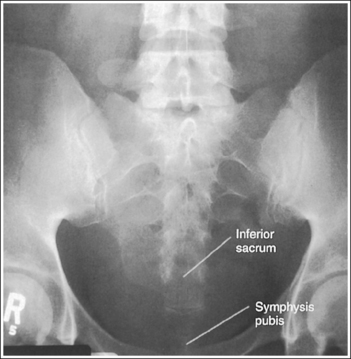

Sacroiliac Joints: Anteroposterior Axial Projection

See Figure 7-32 and Box 7-7.

The sacroiliac joints are demonstrated in an AP axial projection. The median sacral crest is aligned with the symphysis pubis and the sacrum is at an equal distance from the lateral wall of the pelvic brim on both sides.

• An AP axial projection of the sacroiliac joints is obtained by positioning the patient supine on the imaging table with the legs extended. Position the patient's shoulders and ASISs at equal distances from the imaging table to prevent rotation (Figure 7-33).

• Detecting sacroiliac joint rotation. Rotation is detected on an AP axial sacroiliac joint projection by evaluating the alignment of the long axis of the median sacral crest with the symphysis pubis and the distance from the sacrum to the lateral pelvic brim. When the patient is rotated away from the supine position, the sacrum moves in a direction opposite from the movement of the symphysis pubis and is positioned next to the lateral pelvic brim situated farther from the imaging table. If the patient is rotated into an LPO position, the sacrum is rotated toward the patient's right pelvic brim. If the patient is rotated into an RPO position, the sacrum rotates toward the patient's left pelvic brim.

The sacroiliac joints are demonstrated without foreshortening and the sacrum is elongated, with the symphysis pubis superimposed over the inferior sacral segments.

• The patient is positioned supine, with the legs extended, and the lumbosacral curve causes the proximal sacrum and sacroiliac joints to be angled 30 to 35 degrees with the imaging table and IR. To demonstrate the sacroiliac joints without foreshortening, a 30-degree cephalic angle should be used for male patients and a 35-degree cephalic angle for female patients. Patients with less or greater lumbosacral curvature will require a decrease or increase, respectively, in cephalic angulation to maintain the 30- to 35-degree alignment of the central ray and sacroiliac joints. If an AP axial sacroiliac joint projection is taken with a perpendicular central ray or without enough cephalad angulation, the sacroiliac joints and the first through third sacral segments are foreshortened (see Image 23). If the AP axial sacroiliac joint projection is taken with too much cephalic angulation, the sacrum and sacroiliac joints demonstrate elongation and the symphysis pubis is superimposed over the inferior aspects of the sacrum and sacroiliac joints (see Image 24).

The second sacral segment is at the center of the exposure field. The sacroiliac joints and the first through fourth sacral segments are included within the collimated field.

• Center the central ray to the patient's midsagittal plane at a level 1.5 inches (3 cm) superior to the symphysis pubis. Center the IR to the central ray, and open the longitudinal exposure field to the symphysis pubis. Transversely collimate to approximately a 9-inch (22-cm) collimated field size.